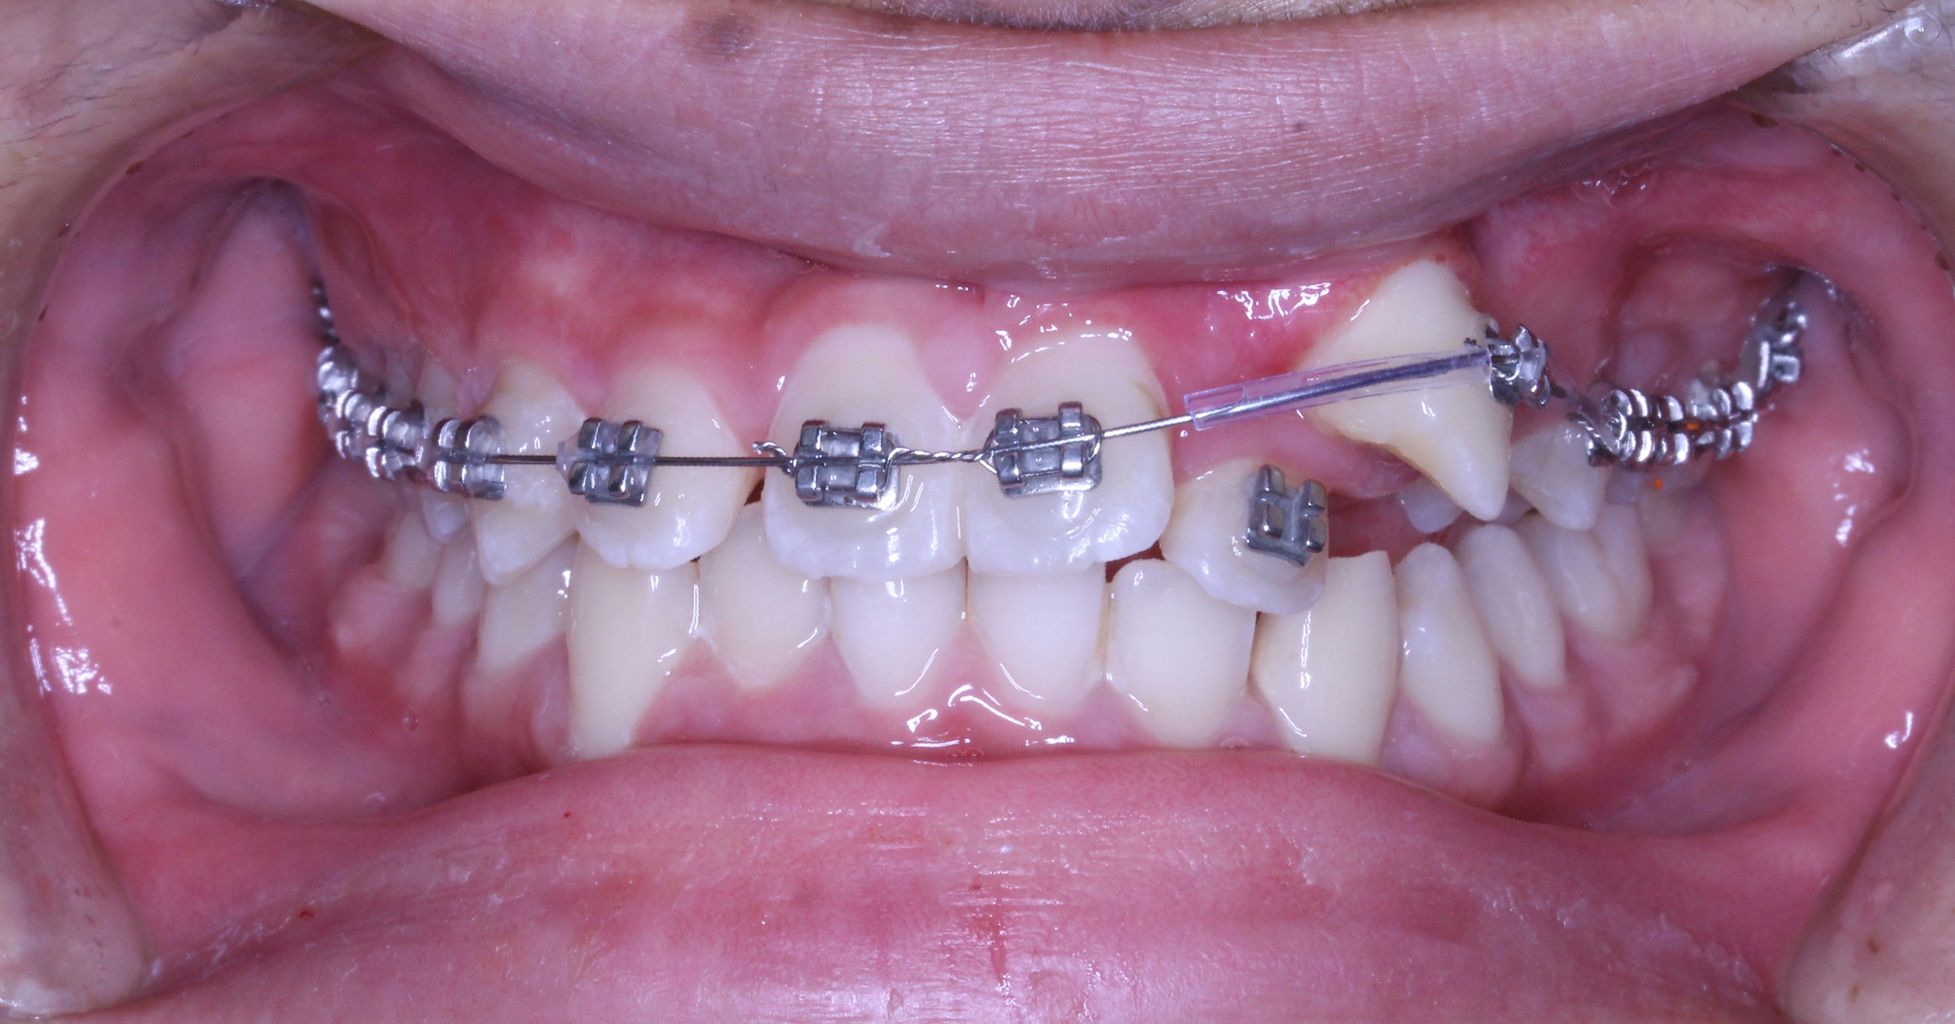

現在の状況はもう少し治療が進んでいるのですが、矯正歯科ネットユーザー様からの質問が昨日でしたので、数か月前の記録ですが、現在の進行状況です

正面と側面の写真をみてもあまり変化がわからないと思います。

上からみてみるとどうでしょうか?

もう少し犬歯が後方に移動してもらえると、2番目の歯が前方に移動可能な感じです